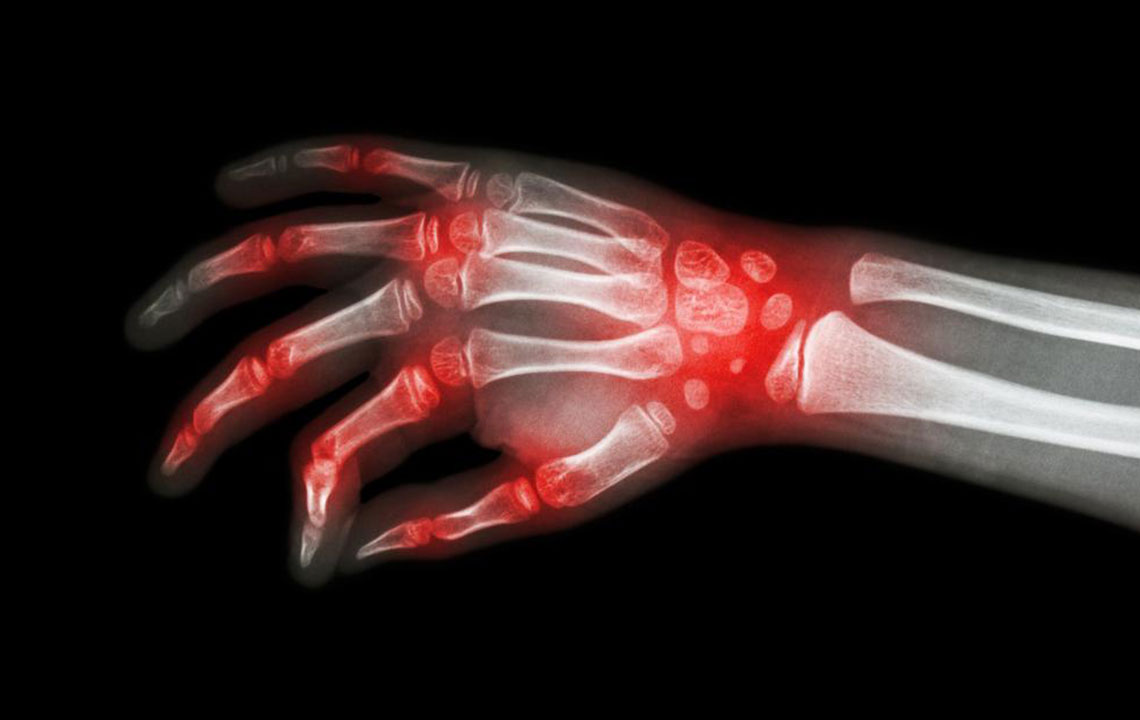

Rheumatoid-arthritis-and-lupus-what-makes-them-similar